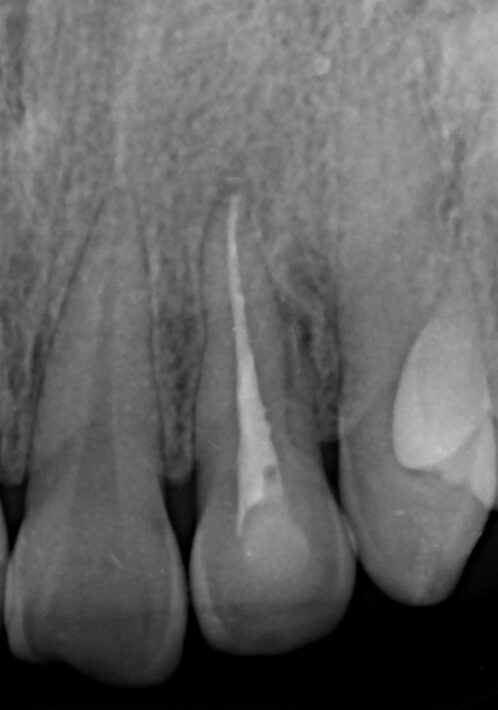

Traitement en cours = Longueur OK

Final J0

Radio à 1 an = C’est gagné ! ( pour l’instant! )